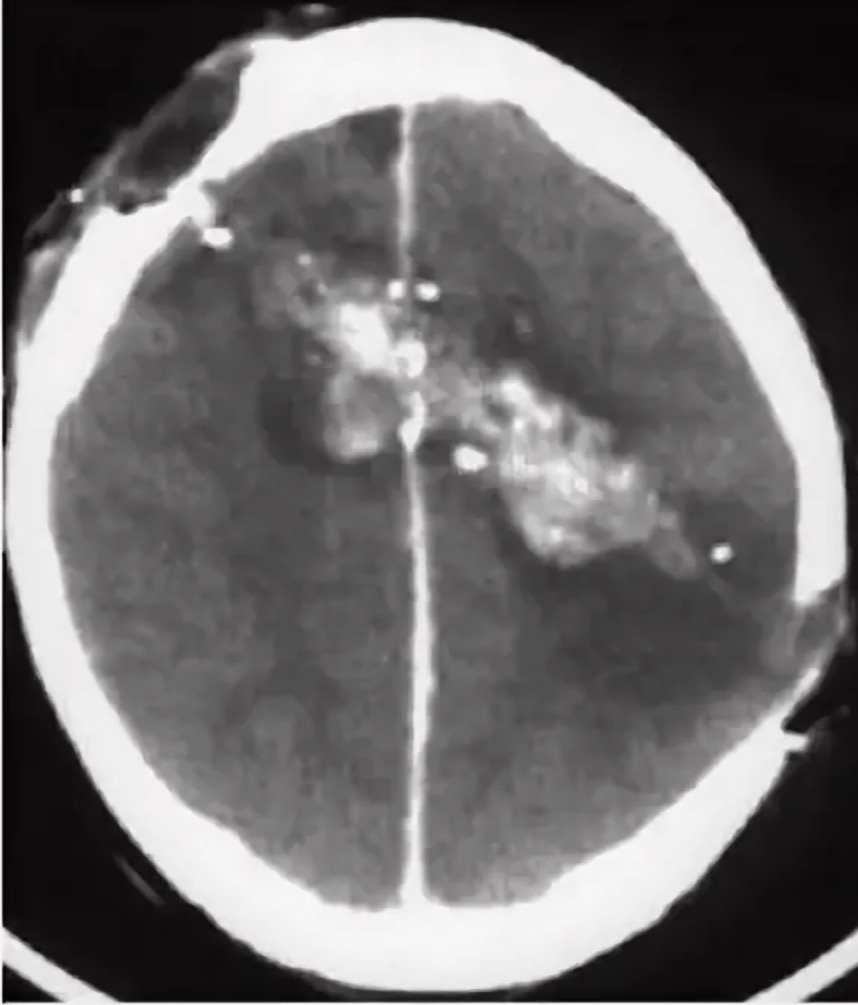

КТ пациента с диаметральным пулевым ранением черепа и головного мозга. На момент снимка - эпилепсия не его главная проблема. Но в будущем она также у него возникла.

Травмы головного мозга, которые могут привести к эпилепсии весьма разнообразны. Это как проникающие ранения (огнестрельные ранения, осколочные, колотые холодным оружием), так и состояния после сдавления мозга гематомой в послеоперационном периоде после ее удаления. Существует ли разница – какая будет эпилепсия в зависимости от механизма и типа травмы? Да, но нужно понимать, что течение эпилепсии – это очень индивидуальный процесс и заранее предсказать его детально попросту невозможно!